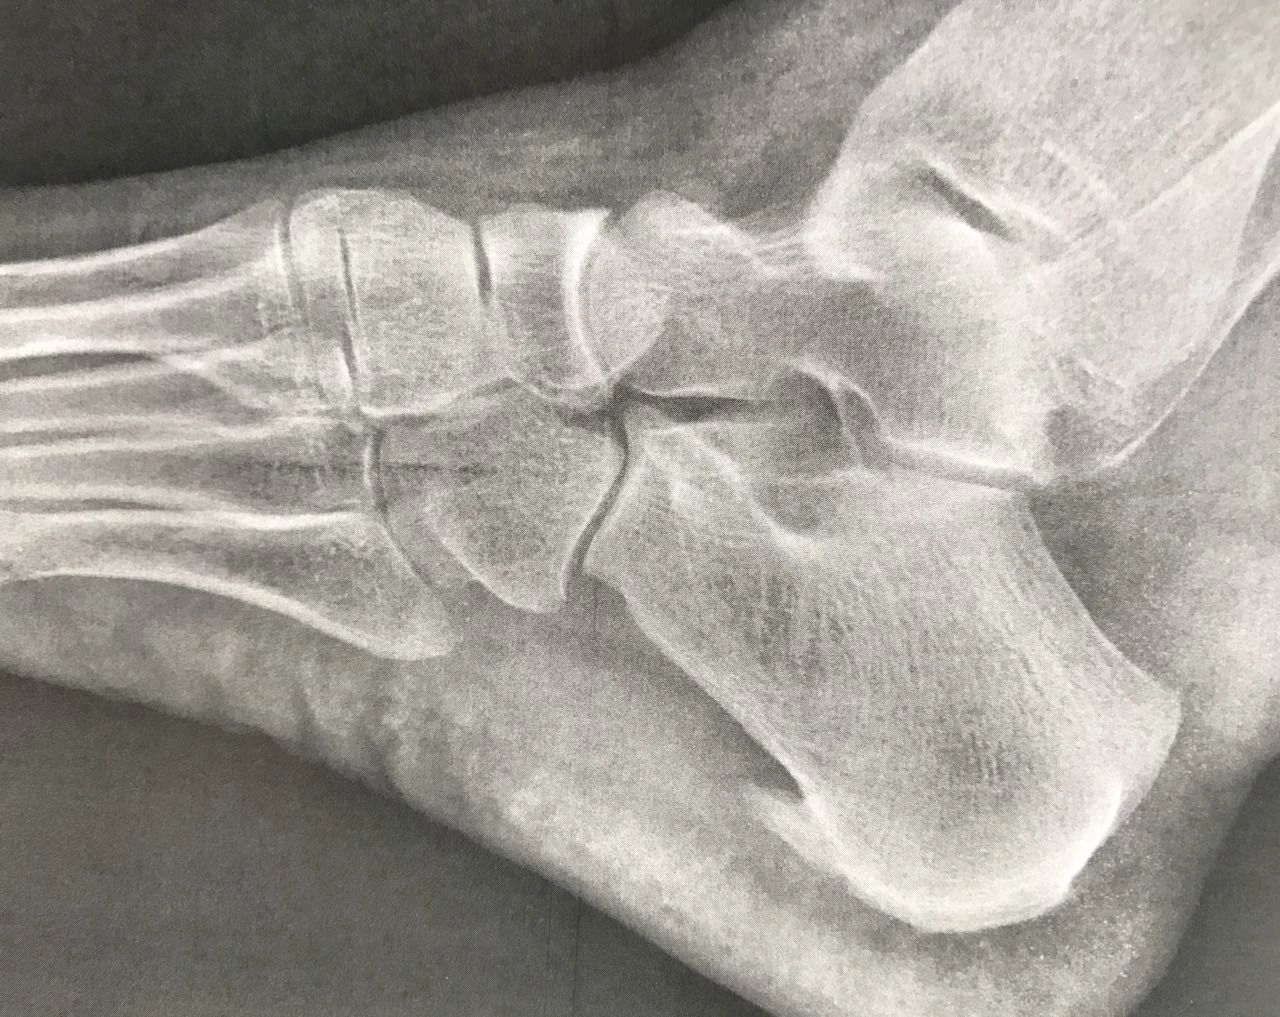

Diagnóstico El espolón se puede diagnosticar con una radiografía lateral del calcáneo, donde se reconoce una protuberancia orientada hacia los dedos y que puede variar entre 1 y 5 mm.